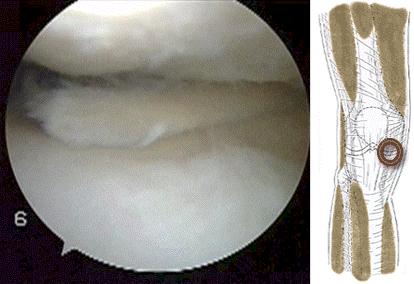

●E瓣状裂:从图像上大家就会明白为什么有这样的称呼了,因为这种半月板的撕裂就形成了一个活瓣,也有人称之为鸟喙(鸟嘴)样的损伤。这种情况由于损伤已经累积了内侧1/3的白区,很难自我愈合。而且一般损伤范围比较广很难进行缝合,一般情况下是手术治疗会进行部分切除成形术。

大家看术中镜下的情况就会明白为什么不能缝合了,这种情况半月板损伤的范围是比较大的,而且涉及了白区。